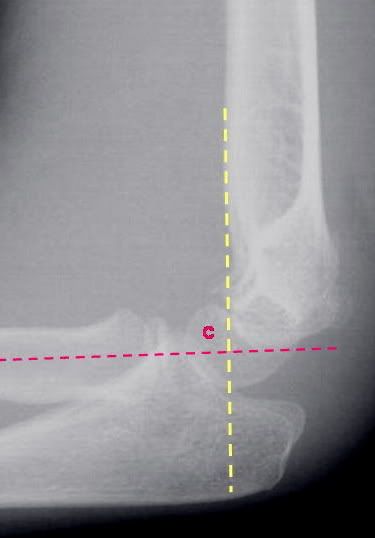

Colles Fracture Dinner Fork

Distal Humerus Fracture